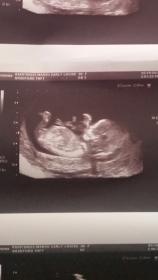

No nub showing :-( Sent from my iPad using Tapatalk

What gestation was this? Think I see nub looking girly and spine curved x Sent from my iPhone using Tapatalk